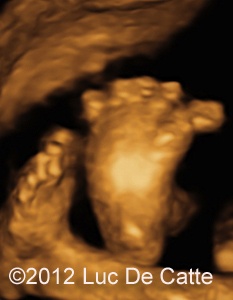

Image 5-7: Exophthalmus and prominent open eyelids; Broad, deviated great toe.

COW_2

COW_3

screenshot_161

• Broad, deviated great toe

The typical craniosyntosis/cloverleaf skull, prominent proptosis and wide great toe suggested Pfeiffer syndrome.

With the major abnormalities, the unfavorable prognosis was discussed with the patient. The couple opted for a termination of pregnancy at 28 weeks and 6 days. The postmortem examination confirmed our diagnosis. The autopsy showed a male fetus of 1330gr. There was a cloverleaf skull with preterm synostosis of the lambdoidal suture, sagittal suture and coronal suture. The frontal suture (metopic suture) stood widely open. Hypertelorism and proptosis was noticed with open eyelids, corneal clouding and ectropion. The concomitant altered dentinogenesis and varus position of the great toes (broader and longer) suggested Pfeiffers syndrome.